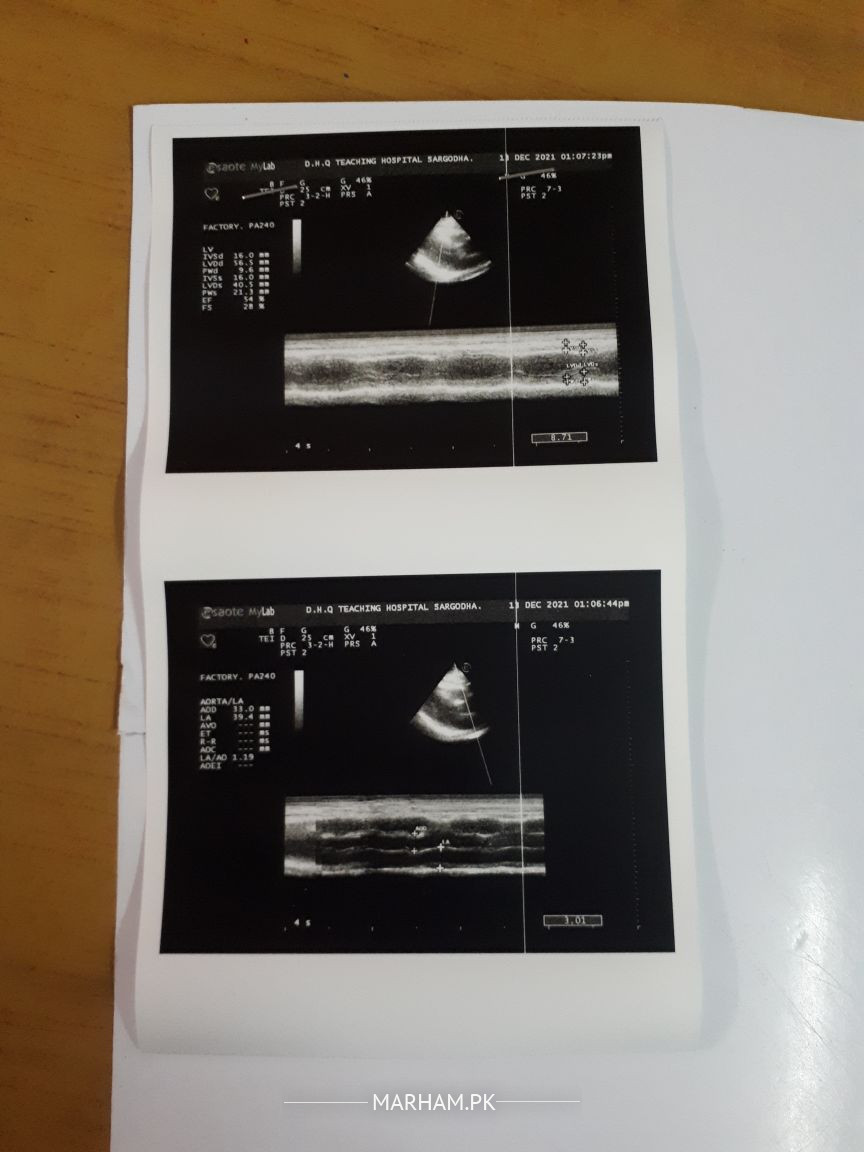

Echocardiography report is attached please check and tell me what is the problem/disease or is there any serious problem?

in simple words report conclusion is almost normal heart pumping function but your father has problem in blood vessel supply to heart.. it needs more investigation and clinical assessment.

Thanks for consultation. Echocardiography of the patient is within the normal limits. It will be better to ask the patient what he has complaints. ECG will be helpful.  If he has any problems with breathing or chest pain or palpitation, then he should  e further investigated. Echo shows normal report.